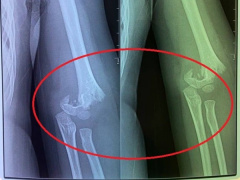

Học sinh lớp 2 bất ngờ ngã từ lan can xuống sân trường, gãy cả 2 tay

Khi đang trèo qua lan can hành lang của trường tiểu học, một em học sinh lớp 2 bị ngã xuống đất, gãy cả 2 tay.

Bé gái 5 tuổi đi mẫu giáo bị bạn đẩy ngã gẫy tay nhưng cô giáo không đưa đi cấp cứu ngay, người mẹ chia sẻ: Nhà trường bặt vô âm tín!

Điều quan trọng là con bị ngã gẫy tay từ sáng mà đến 12h trưa giáo viên mới cho con đi bệnh viện. Lúc con ngã, cô không đưa đi khám luôn mà lại đưa con vào lớp, để các bạn ăn uống xong xuôi rồi mới gọi một chiếc xe tư nhân đưa con đi mà không phải xe cấp cứu, chị H. bức xúc cho biết.